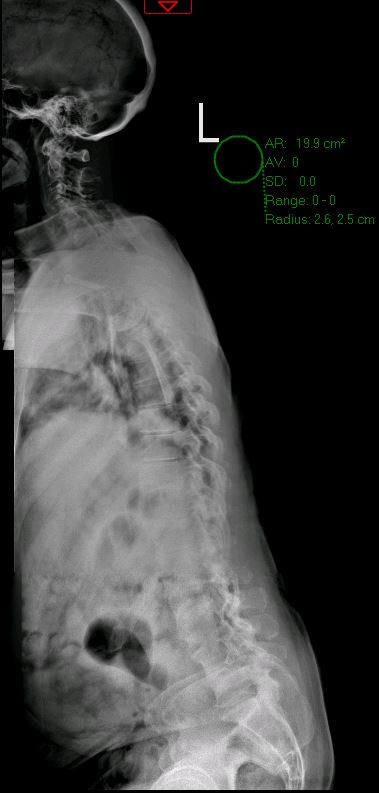

Before & After

Spine Surgery

De-identified imaging from complex spine surgery cases. Each pair shows pre-operative pathology alongside post-operative correction across cervical, lumbar and deformity subspecialties.